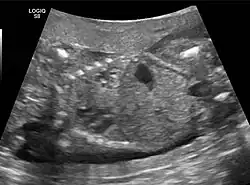

- Congenital pulmonary airway malformation in a fetus, ultrasound at 19 weeks -sagittal. Stomach top right of image, heart displaced to bottom left of image (anatomically on the right side of fetus.)

- Congenital pulmonary airway malformation in a fetus, ultrasound at 19 weeks - transverse. Stomach on left image; heart on right image: displaced to right by cystic mass